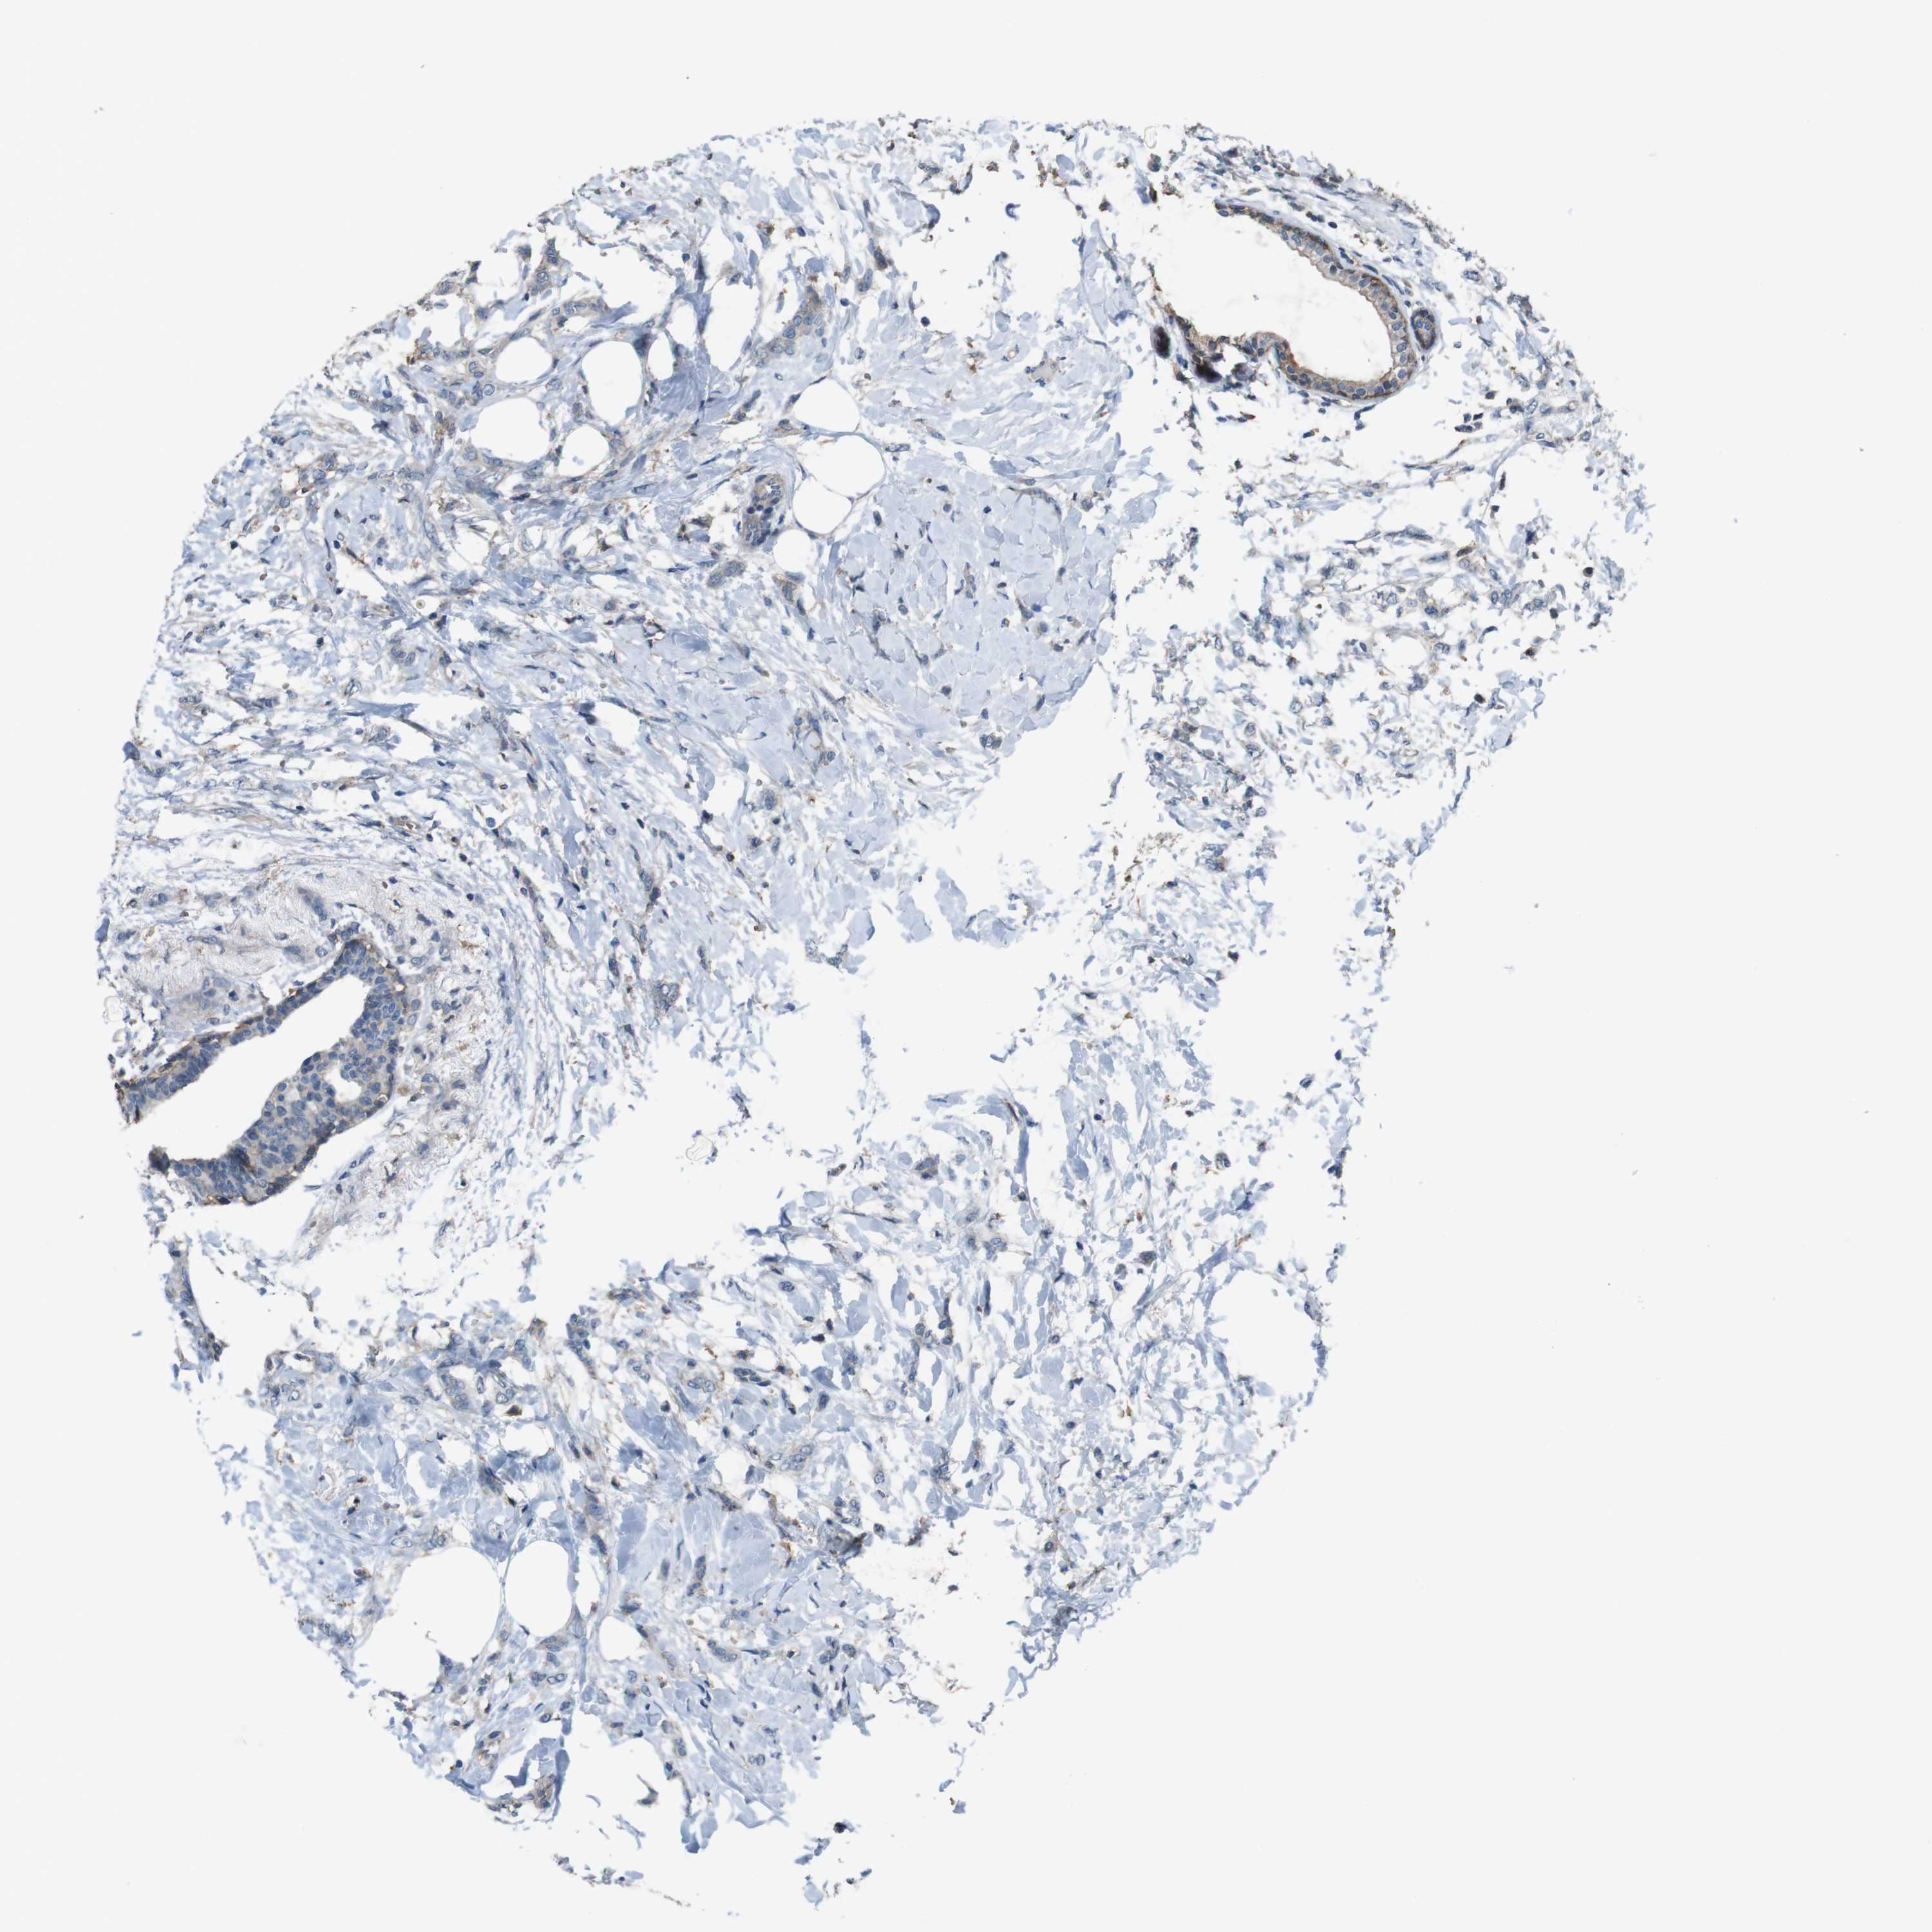

BRCA TCGA BRCA VALIDATION PROTEIN EXPRESSION